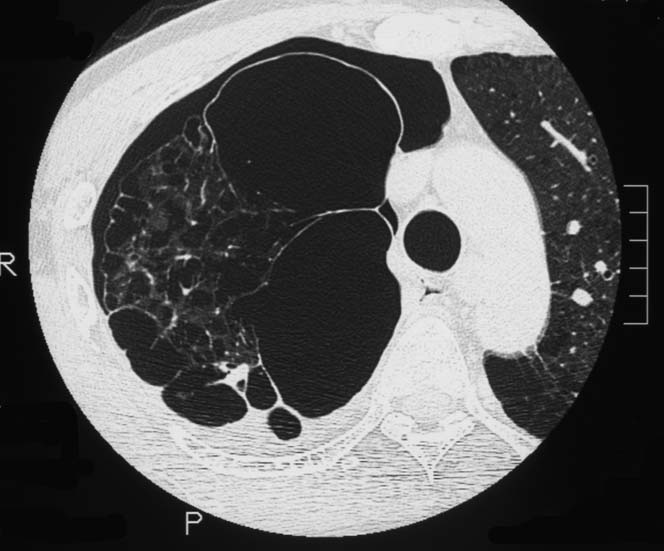

初診から11ヵ月, 胸部つかえ感出現. CTで気管分岐部から横隔膜食道裂孔を通り, 腹腔内へ進展, 食道および大動脈を囲繞する巨大な腫瘍が再発した. 他院での抗がん剤感受性テストの結果より, CDDP+5FUによる化学療法がおこなわれたが効果乏しく全身状態悪化. 呼吸不全が進行し初診より約1年の経過で永眠された.